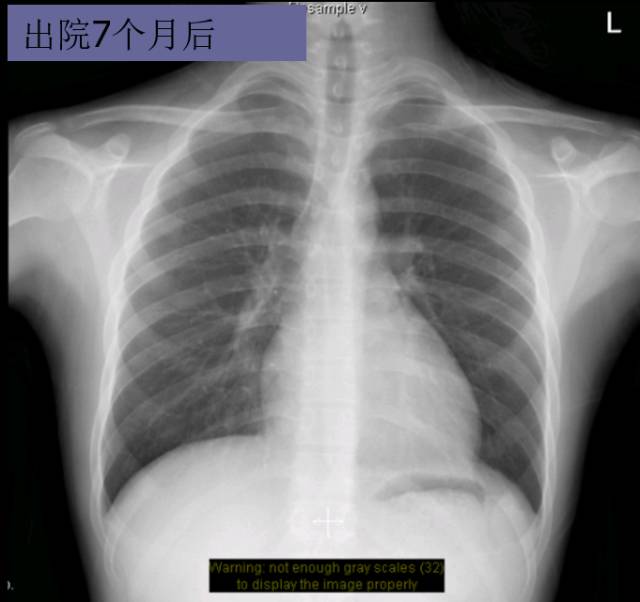

随访转归

► 7月后复查:心脏缩小,心功能好转

► 2年后病情平稳,复查超声心动图、NT-proBNP等大致正常。仅口服比索洛尔10mg qd+贝那普利5mg qd

► 3年后复查HOLTER:频发房早32925次,短阵房速。 患者心率控制在70-90bpm,超声心动图依然大致正常。未再出现胸闷,浮肿等症状。

► 6年内多次复查,UCG正常。无心衰症状。

► NT-proBNP 8787.94pg/ml(入院时)→540.1pg/ml(1年后)→ 378.4pg/ml(2年后),后多次复查均正常